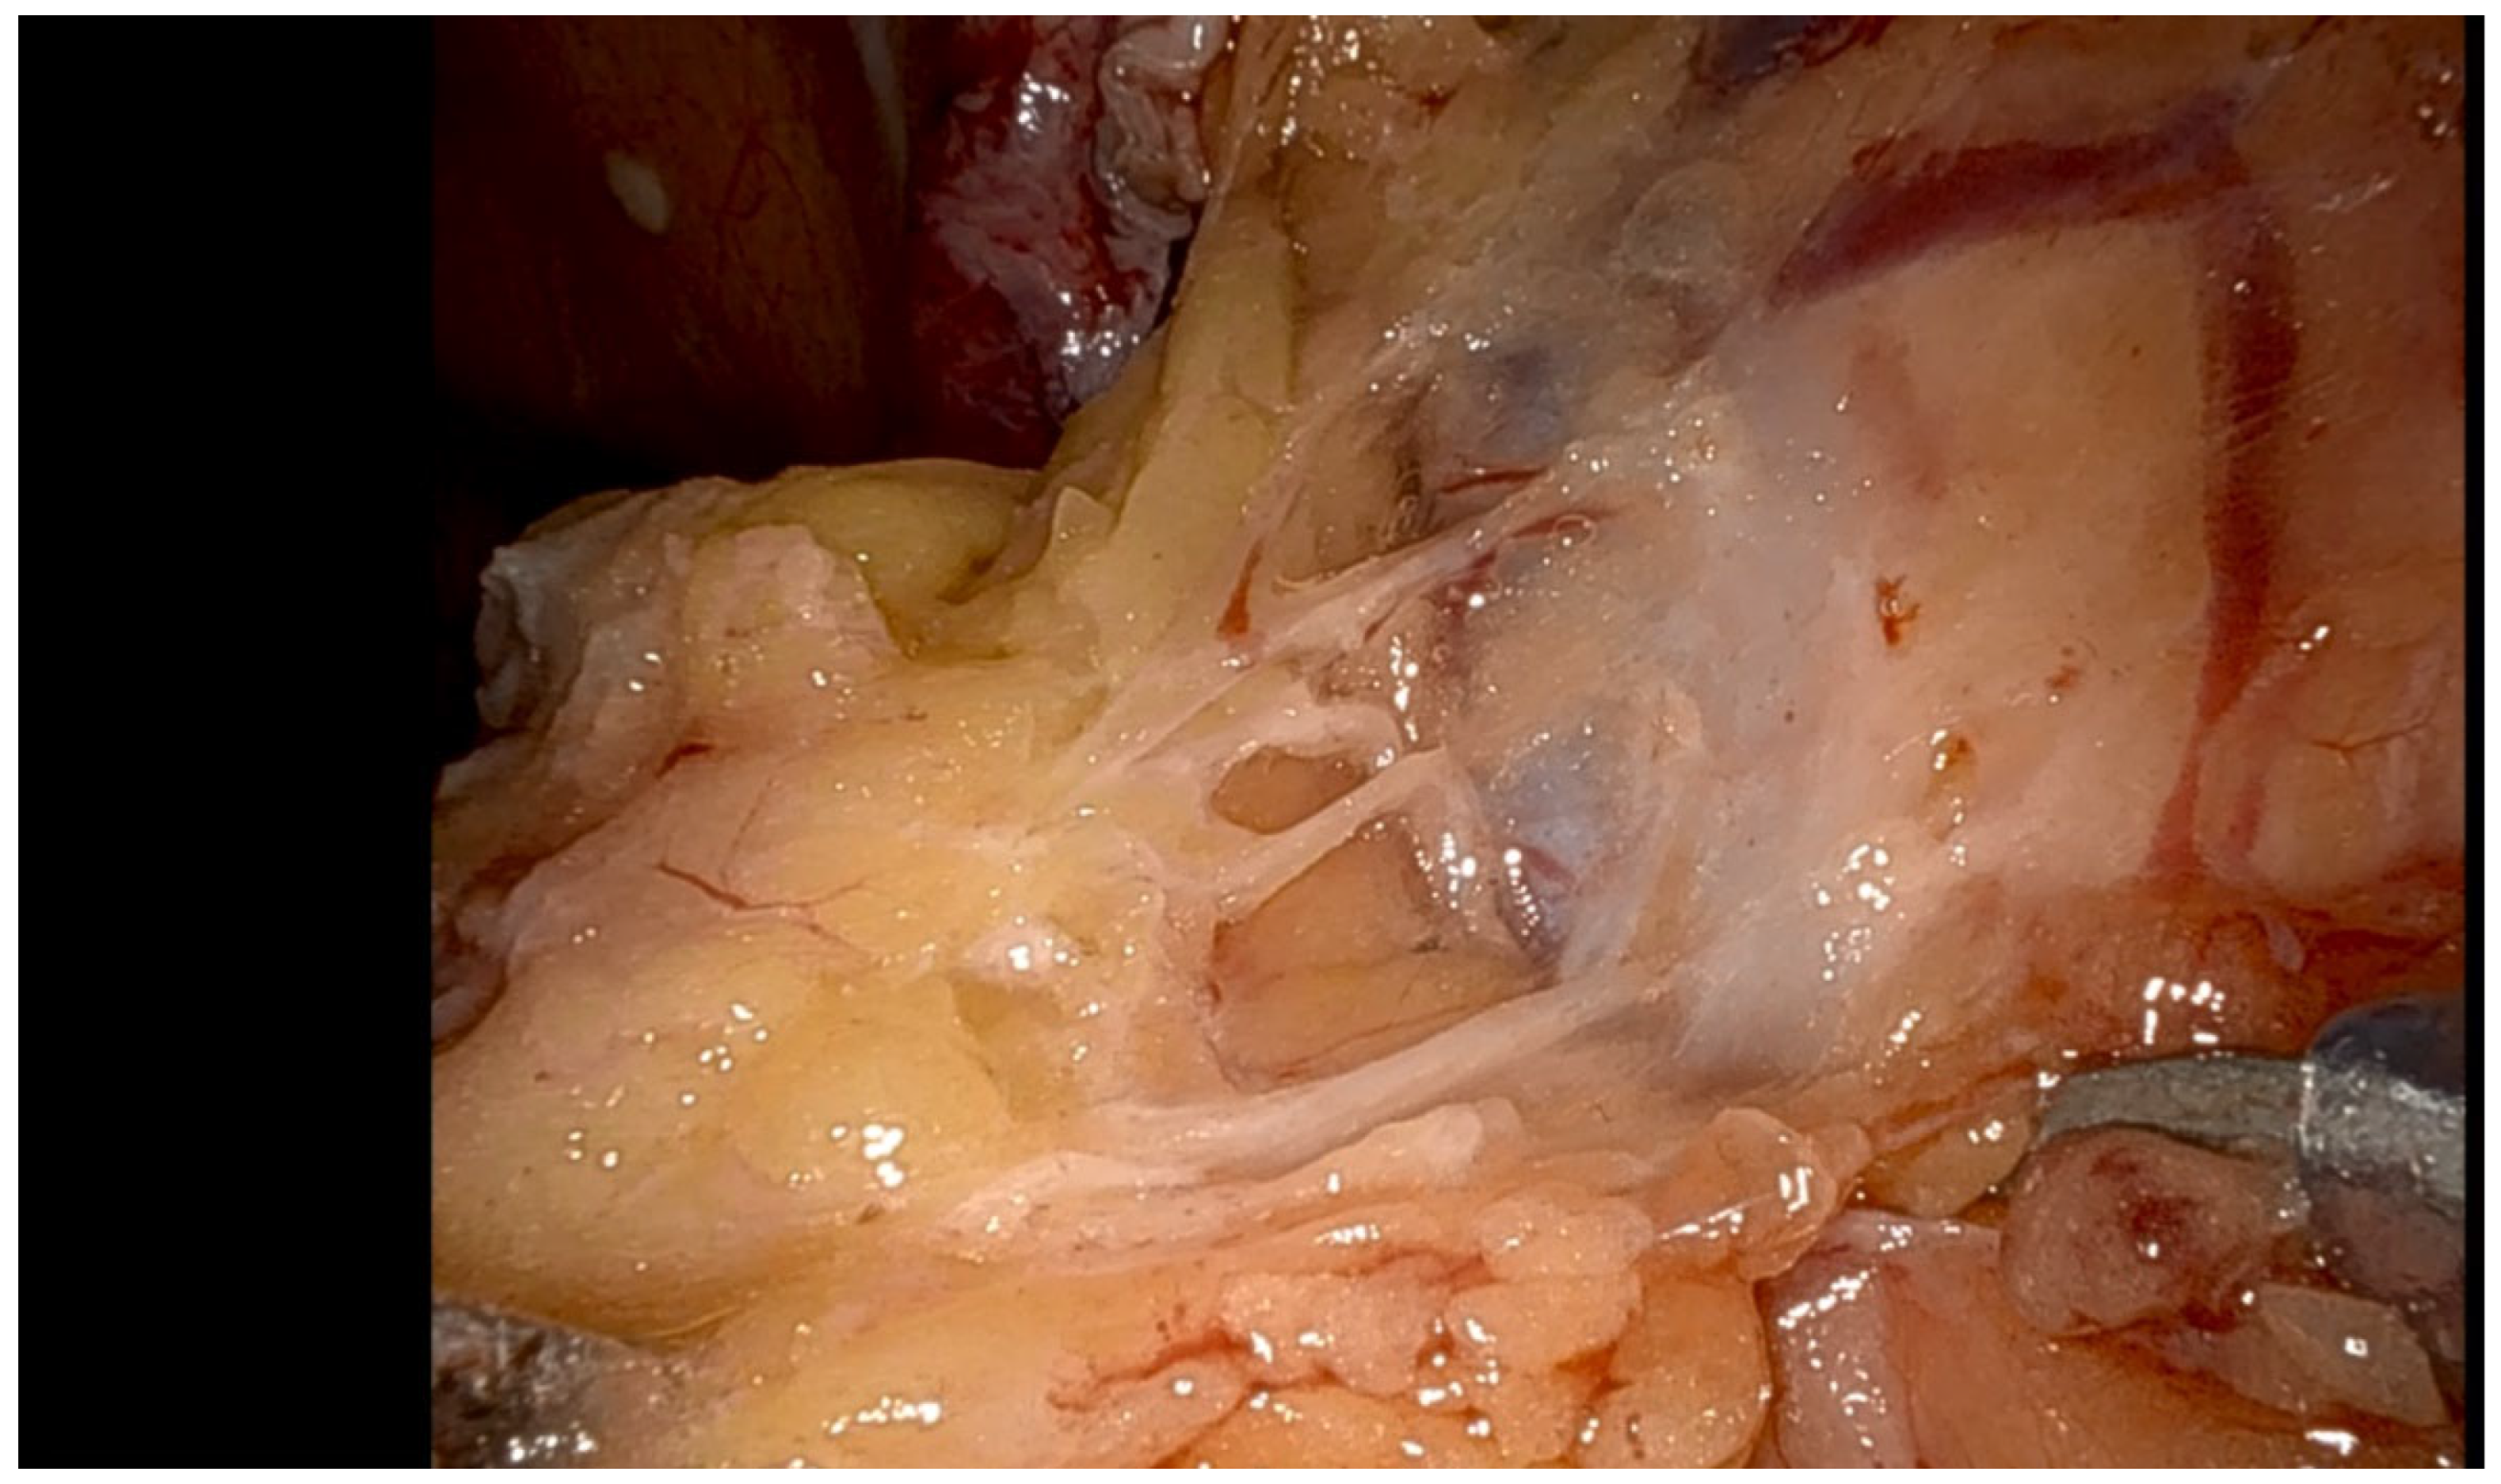

- Borderline ovarian tumors; a paradigm shift

- Pelvic saline infusion (500 mL) creates an acoustic window for enhanced ultrasound transmission.

- Transvaginal or laparoscopic probes provide multiplanar tumor localization.

- Laparoscopic instruments mark lesion boundaries under dual visual-sonographic guidance.

- Diathermy delineates precise resection margins before ultrasound-monitored excision.